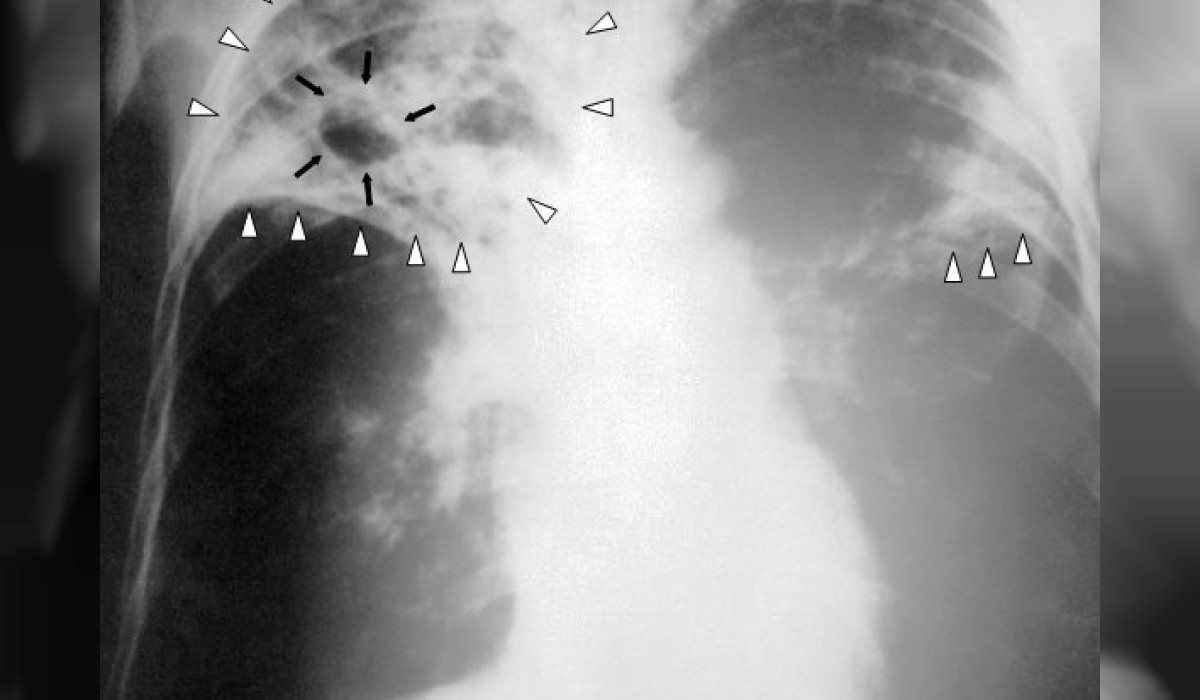

Өлкөдө жасалма интеллекттин жардамы менен кургак учук илдети аныкталууда. Бул тууралуу улуттук фтизиатрия борборунун директору Абдулаат Кадыров "Биринчи радиого" билдирди.

"Кыргызстанда Бүткүл дүйнөлүк саламаттыкты сактоо уюмунун көрсөтмөсү менен кургак учукту аныктоодо 2 жылдан бери санарип рентген аппараты жасалма интеллекттин жардамы аркылуу колдонулуп жатат.

Бүгүнкү күндө өлкөдө мындай 4 аппарат бар. Мунун жөнөкөй рентгенден айырмасы адамга тийгизген терс таасири аз",- деди ал.